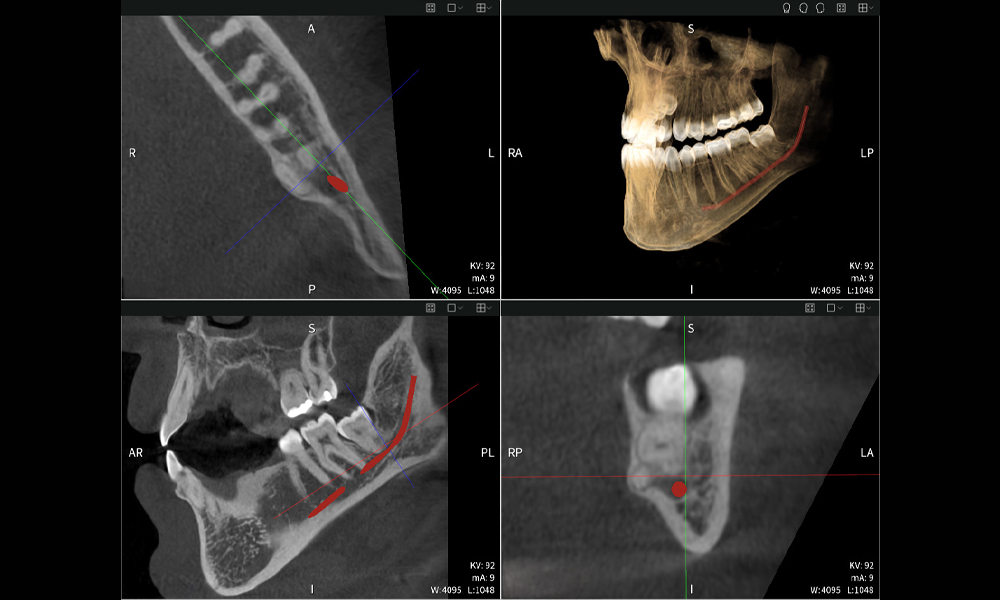

Below you will find a case from Dr. med. dent. Oliver A. Centrella, in which the CBCT images obtained with Seethrough Max provided crucial information on the complex anatomy and the critical relationship between the wisdom teeth and the inferior alveolar nerve. In this case, there is a indication for the surgical removal of the wisdom teeth.

Figure a

- Top left: Axial cross-section of the left mandible (region 38) showing the inferior alveolar nerve (red) in proximity to the roots of tooth 38.

- Top right: 3D reconstruction of the entire mandible for orientation. The red-marked inferior alveolar nerve illustrates its location within the jawbone.

- Bottom left: Sagittal view of the mandible (region 38), highlighting the close spatial relationship between the roots and the nerve canal.

- Bottom right: Coronal view of the mandible (region 38), which is crucial for assessing the spatial position of the roots relative to the nerve.

Figures b–d show various views of a 3D reconstruction of the mandible, providing a comprehensive overview of the mandibular anatomy, the position of the nerves in relation to the teeth, and allowing assessment of tooth symmetry and alignment.